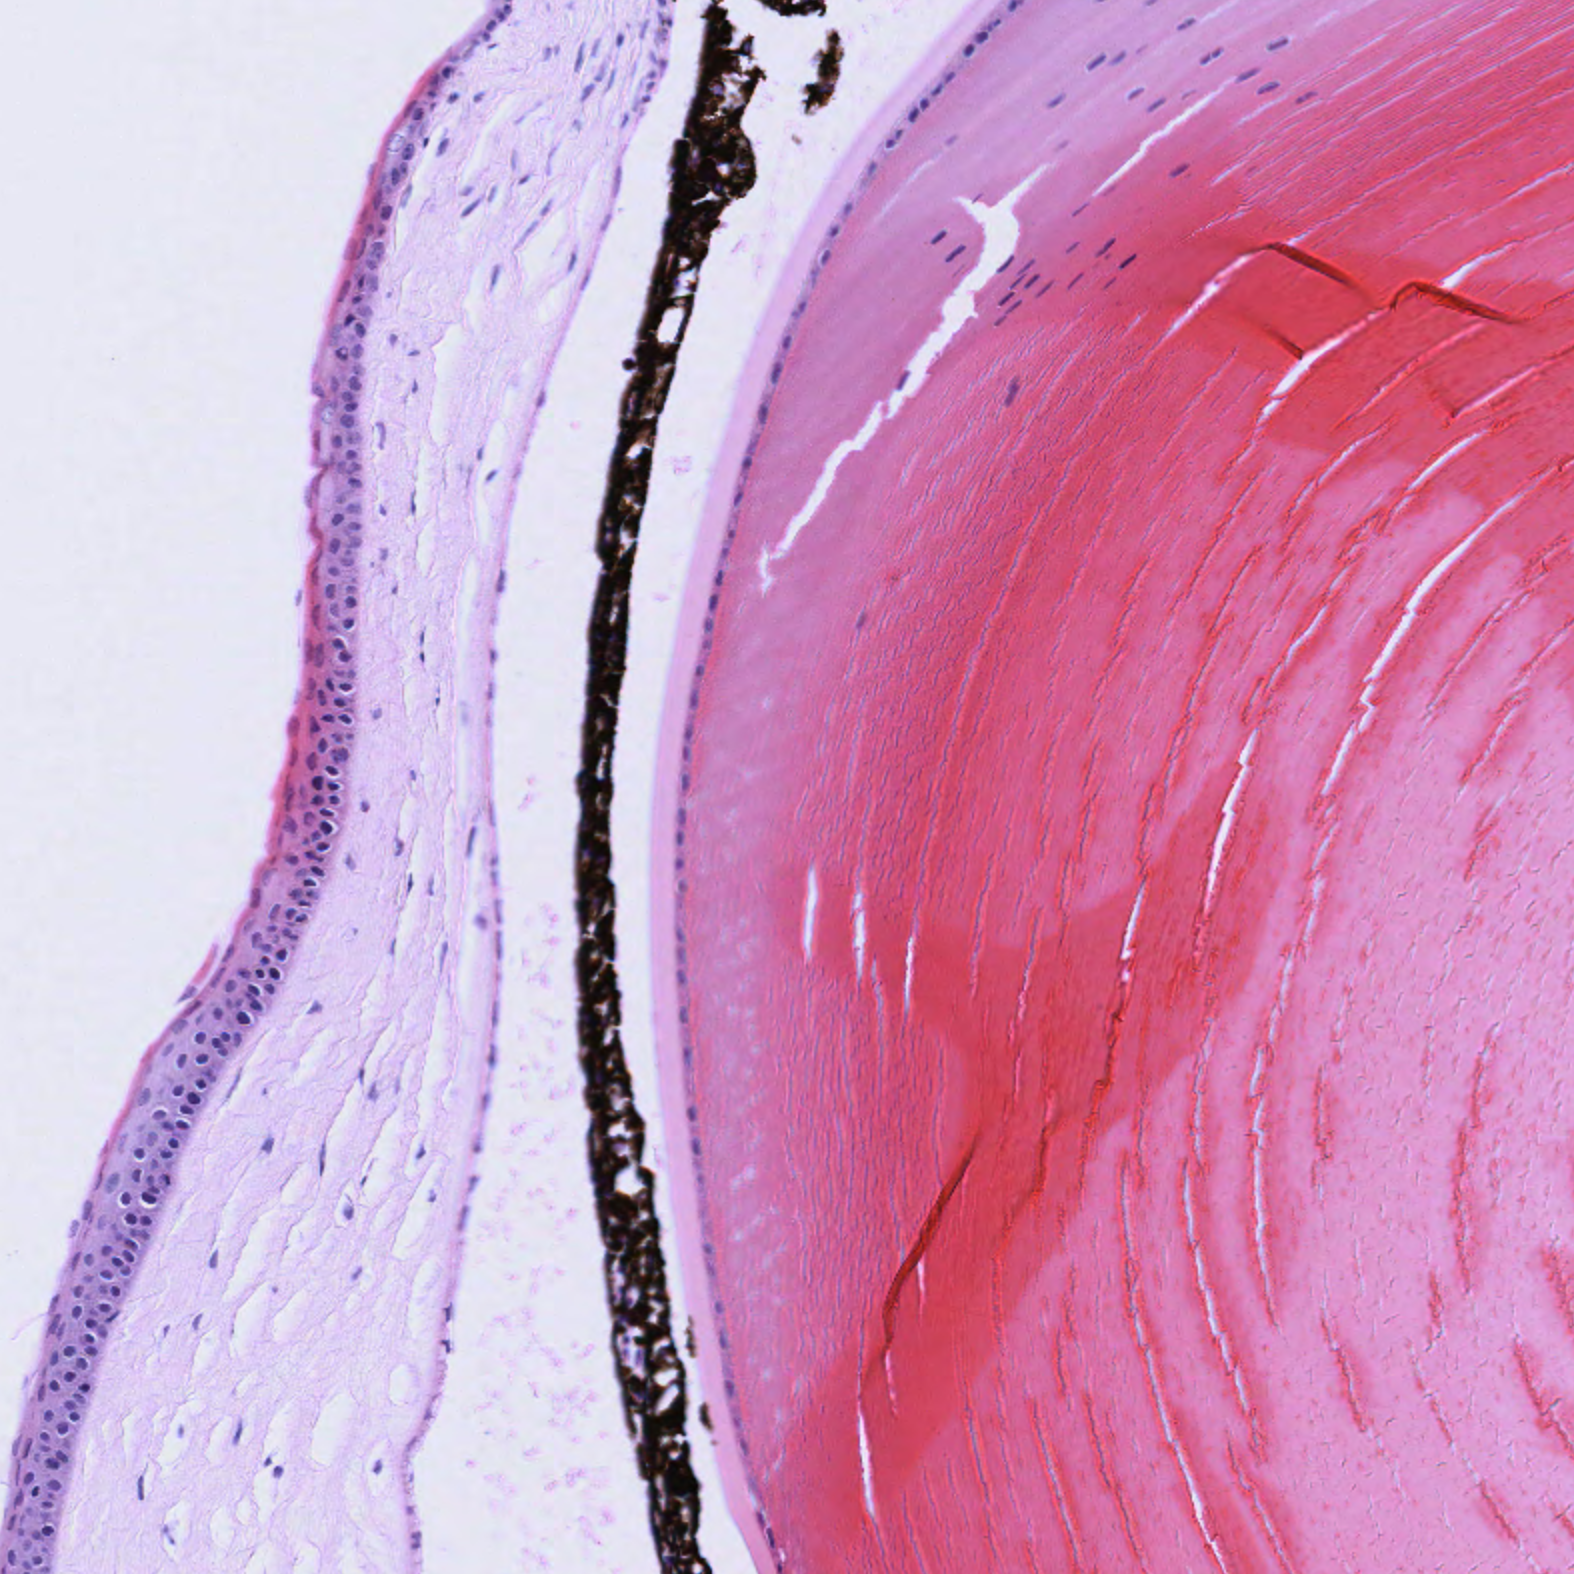

Cornea

| Eye_Cornea_H&E_02.svs Eye_Cornea_H&E_02.png |

Eye_Cornea_Pen_02.svs Eye_Cornea_02.png |

The corneal layers are better visualized using the pentachrome stain kit. The pentachrome stain kit also finely stains the rod cells and allows for easy differentiation of the microstructures of the retina and cornea. The pentachrome stain kit is therefore a finer stain for the fibrillar structures. However, the nuclear staining is not as strong and the inflammatory cells might be less precisely identified.